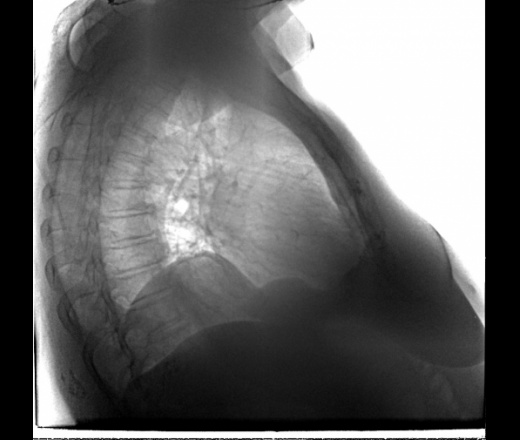

Бабушка 1940 г р. Жалоб нет. Так давление высокое,сердишко пошаливает да пенсия маленькая...Проф ФЛГ.  Со слов кроме как терапевта ни кого больше не посещает,да и то за рецептами...,на учёте у докторов не состоит. Последнее ФЛГ в 2013г написали релаксация правого купола диафрагмы,возрастные изменения. Коллеги ну это не релаксация ведь? Помогите пожалуйста разобраться.

Релаксация

Спасибо! необычно выглядит как то:)

Бывает локальная (парциальная) релаксация.

А вот это что за тень может быть:(?

Диафрагма. Диафрагма справа "двугорбая", слева - "одногорбая".(имею ввиду, на представленном снимке)